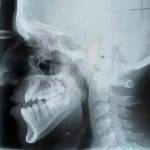

نجح فريق طبي في مشفى الشرطة بدمشق اليوم بإجراء عمل جراحي دقيق لشاب في الرابعة عشرة يعاني نقص نمو في النصف الأعلى من الوجه باستخدام تقنية موسعات “زوريش” البانية للعظم ذاتيا والتي تستخدم لأول مرة في سورية.

وفي تصريح لمندوبة سانا بين رئيس الفريق رئيس شعبة جراحة الفكين بالمشفى الدكتور خالد العوف إن المريض يعاني حالة نقص نمو في منتصف الوجه ناتج عن تشوه خلقي يزداد مع تقدم العمر ويسبب مشاكل نفسية وعضوية تتمثل بصعوبة التنفس والكلام والأكل موضحا أن العملية أجريت بتقنية خاصة تستخدم لأول مرة في سورية وهي غير متوافرة محليا حيث تكفل المشفى بتأمينها.

ولفت الدكتور العوف أن العملية تمت بمشاركة أربعة أطباء مقيمين بتخصص الجراحة الفكية بالمشفى واستمرت خمس ساعات مبينا أن هذه الموسعات تسهم في بناء الفك وتوسيعه نحو الأمام وهي مصنوعة من مادة التيتانيوم وذات تكلفة عالية.

وبحسب الدكتور العوف إن التقنية المستخدمة تسهم بتوسع عظم الفك بشكل يومي 1مم وتحدد حاجة التوسيع حسب حالة كل مريض حيث يحتاج المريض الذي أجريت له العملية إلى عشرين يوما لضمان توسع بـ20 مم يتم بعدها تثبيت الموسعات ومن ثم إزالتها جراحيا بعد ستة أشهر.